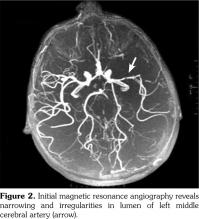

Based on these clinical findings, the patient was diagnosed as HSP, and the skin biopsy showed leukocytoclastic vasculitis with histopathologic evidence of immunoglobulin (Ig) A and M deposition based on direct immunofluorescence staining. A written informed consent was obtained from the parent of patient. The patient was being followed-up as an out-patient. On the 15th day of his follow-up, he admitted to the emergency department by sudden focal tonic- clonic convulsions and unconsciousness. He was not able to use his right hand and foot, also he could not talk. His blood pressure was 105/70 mmHg. Fundoscopic examination was unremarkable. The physical examination showed aphasia, right sided central facial paralysis, and hemiplegia on the right. Deep tendon reflexes were exaggerated and there was extensor plantar response on the right side. Cerebellar functions and sensory testing were normal. In acute laboratory evaluation, serum electrolytes and glucose levels were normal. Immediate 1.5 Tesla magnetic resonance imaging (Magnetom Avanto, Siemens Medical Solutions, Erlangen, Germany) demonstrated multiple, high signal intensity areas on T2-weighted images in both cortical and subcortical areas of the left parietal lobe (Figure 1). Magnetic resonance angiography revealed narrowing and irregularities in the lumen of left middle cerebral artery resembling vasculitis (Figure 2). Electroencephalography showed diffuse generalized delta slow waves of moderate amplitude without epileptiform discharges. Renal angiography and mesenteric vasculature were normal. The patient was diagnosed as cerebral vasculitis due to HSP. Intravenous pulse methylprednisolone (30 mg/kg/day) was given for three consecutive days; subsequently the patient received oral steroids (2 mg/kg/day) for cerebral vasculitis. Because of the unchanged clinical status of the patient, pulse cyclophosphamide therapy was begun. Patient received 500 mg/m(2)/day pulse cyclophosphamide monthly for three months. He showed clinical improvement after cyclophosphamide therapy. The follow-up magnetic resonance angiography, performed 15 days after the initial one, demonstrated substantial improvement of cerebral lesions (Figure 3). His steroid treatment was stopped by tapering within six months. He had speech therapy and also physical rehabilitation and therapy for two years. He has been followed-up without any sequel for four years.

In conclusion, cerebral vasculitis should be suspected in all cases of HSP with neurologic manifestations. Magnetic resonance angiography is the modality of choice for diagnosis and follow-up evaluation. Although treatment options are numerous and controversial, combined therapy with pulse corticosteroid and pulse cyclophosphamide should be the first choice in pediatric patients.